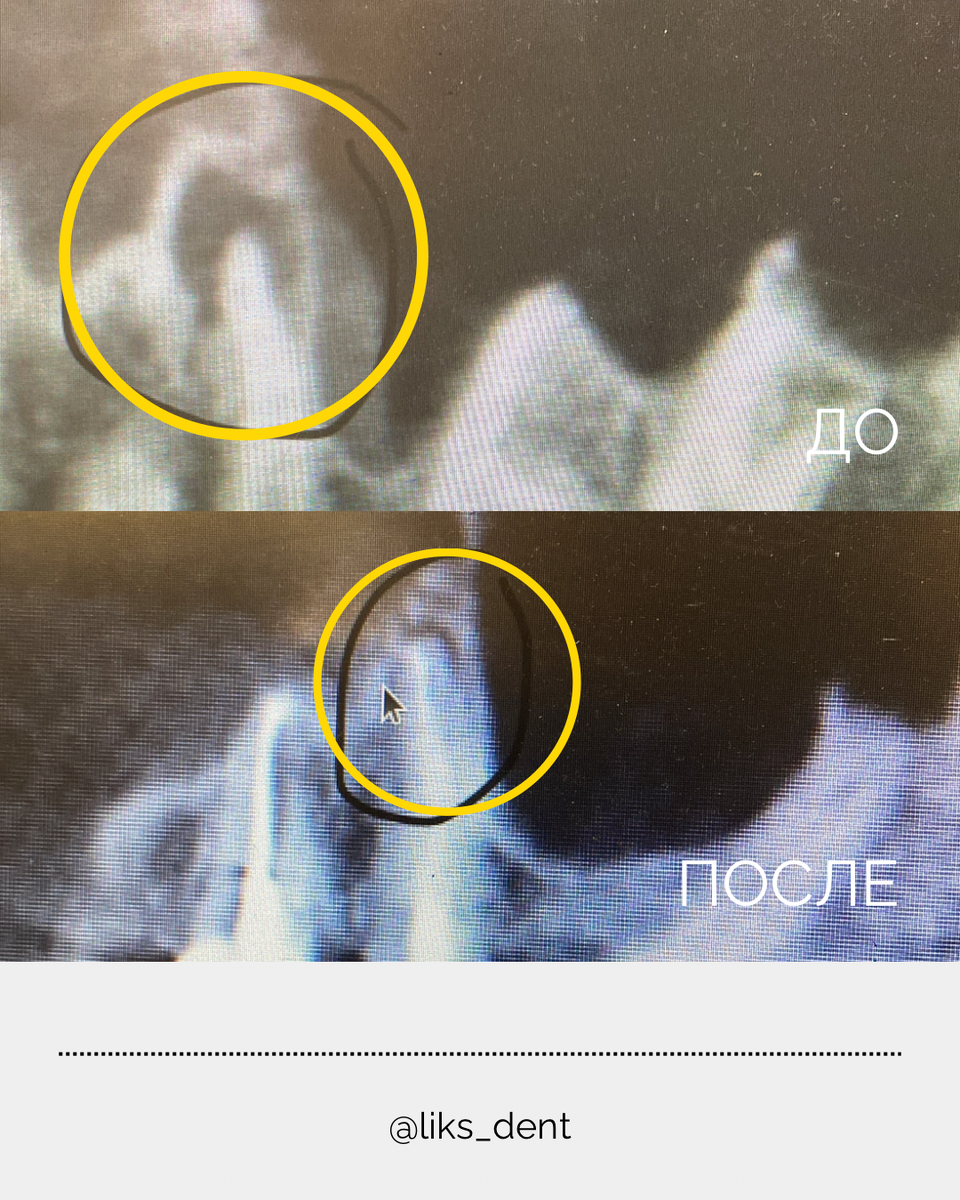

Пациент обратился с жалобами на боль при накусывании и выпадение пломбы. После проведения компьютерной томографии (КТ) выяснилось:

• Глубокий кариес дошёл до нерва

• У корня зуба — воспаление и разрушение костной ткани (то, что часто называют «кистой»)

📸 На снимке КТ она выглядит как тёмное пятнышко у корня зуба

Через 6 месяцев контрольная КТ показала отличные результаты — костная ткань полностью восстановилась, воспаление ушло, зуб сохранён. Теперь он полностью функционален, и в дальнейшем планируется его укрепление коронкой, чтобы защитить от разрушения